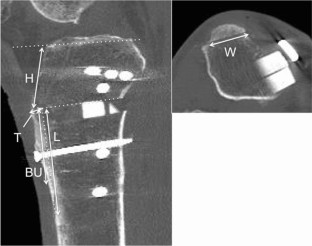

All patients who underwent DTO were retrospectively reviewed, and 104 successive patients were included. The Knee Society Score and complications including tibial tubercle fracture were recorded. On radiographs and computed tomography scans, the length, thickness, width, height, and bony union of the osteotomized tibial tubercle and the posterior tibial slope were statistically analysed.

Fracture of the tibial tubercle occurred intraoperatively in 11 patients (10.6%) and in the postoperative period in 1 (1.0%). The case of postoperative fracture showed non-union. There was no significant difference in the Knee Society Score between the non-fracture and fracture groups. There were significant differences in the posterior tibial slope and the height of the tibial tubercle between the groups (p < 0.0001 for each comparison). The logistic regression analysis showed that the height of the tibial tubercle was associated with a higher risk of the fracture of the tibial tubercle (p < 0.01; OR, 1.548; 95% CI, 1.149–2.085). However, there were no significant differences in the bony union rate of the tibial tubercle at 6 months after surgery between the groups.

Tibial tubercle fracture did not affect the clinical outcome and bony union in spite of the relatively high occurrence rate. Anatomical risk factors for the fractures was a lower tibial tubercle position.